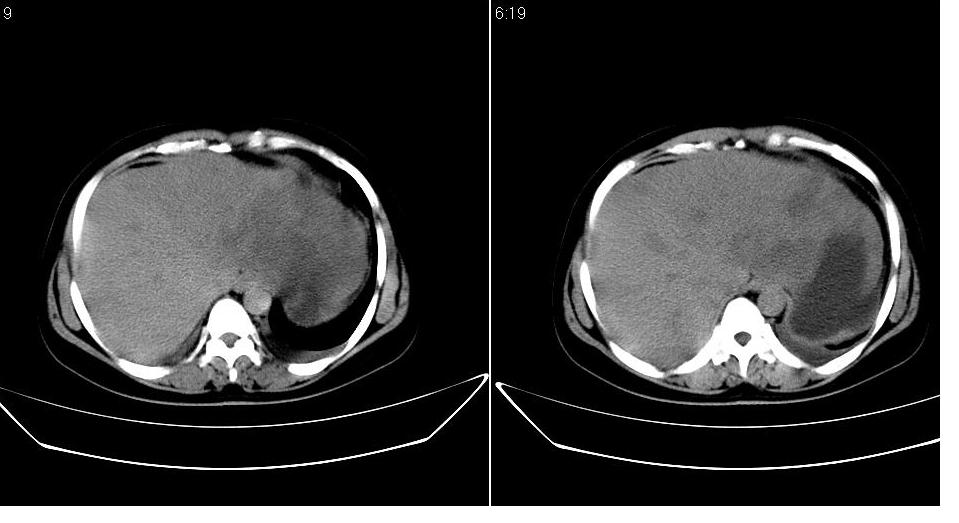

女 36岁,腹痛月余,b超提示肝左叶占位,腹水。

肝脏左叶明显增大,各叶比例失调,左叶实质内不均匀低密度影,似乎有肝内胆管的扩张,没有增强实在不好判断,不知患者肝功能是否正常,我觉得象胆管细胞癌。

1)考虑肝左叶肝癌;建议行进一步检查。2)肝硬化,脾稍大。3)双侧少量胸腔积液。

支持!且患者肝门部有淋巴结转移。

肝左叶占位,建议增强。胸腔积液。